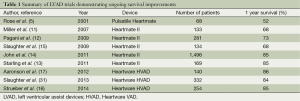

Following the US Food and Drug Administration’s (FDA) approval of the Thoratec Heartmate II CF-LVAD as a BTT in 2008, improvements in survival have continued to increase. One year survival from the initial 133 patients reported by Miller et al. in 2007 was 68% (11). By 2009, this number had climbed to 73% one year survival (12), and by 2011, the one year survival reported by INTERMACS from the postapproval study had climbed to 85% (13) (see Figure 3). Most importantly, patients with CF-LVADs were noted to have improved survival compared with patients supported by pulsatile flow devices (15).

Another CF-LVAD that has demonstrated similar outcomes and improvements in quality of life metrics is the Heartware Ventricular Assist System. HVAD, which utilizes centrifugal flow technology rather than the axial flow design seen in the Heartmate II, is designed with an integrated inflow cannula meant to allow for complete intra-pericardial implantation. The HVAD has consistently demonstrated excellent survival outcomes (16,17), with the ADVANCE trial reporting 86% survival at one year post-implant with a significant improvement in functional capacity and quality of life (17). Compared with optimal medical therapy, the improvements seen in 6-minute walk times was nearly three times better for patients implanted with the HVAD (17,18), further highlighting the dramatic improvements that can be seen with CF-LVAD implantation in heart failure patients.

More recently, CF-LVAD outcomes have continued to improve as our collective experience implantation and post-operative care has grown (Table 1). A retrospective multi-center analysis comparing patients implanted with a Heartmate II LVAD after FDA approval in commercial use with the results from the clinical trial reported a consistent improvement in outcomes (14), with an increase in the percentage of patients who were either transplanted, explanted, or receiving ongoing LVAD support at 6 months and 1 year in the posttrial cohort. Similarly, recently reported figures from patients implanted with the HVAD have also shown remarkable improvements in outcomes, with survival now exceeding 90% at 1 year (31). In fact, the increased utilization of CF-LVADs, along with their excellent long-term outcomes, have led to a decrease in the number of patients transplanted in the first year, from 48% during the Heartmate II BTT clinical trial to only 39% during the post-trial period (14). In this same period, one year survival on the heart transplant waiting list actually increased despite the decreased transplantation rate. This indicates an increase in the number and proportion of patients awaiting heart transplantation after LVAD implantation, further highlighting the feasibility and reliability of extended LVAD support.